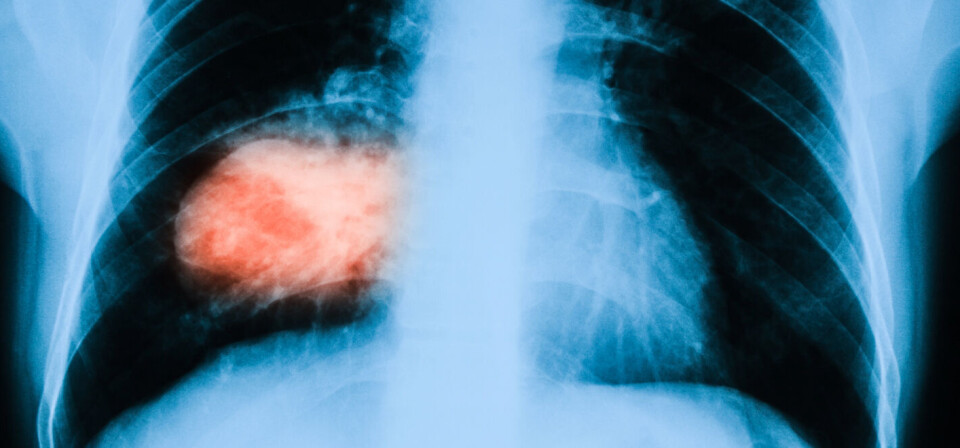

EU-kommisjonen har godkjent det immunterapeutiske kreftlegemiddelet pembrolizumab (Keytruda) som førstelinjebehandling mot ikke-småcellet lungekreft med spredning, hos pasienter der svulsten uttrykker biomarkøren PD-L1. Det kunngjorde MSD tirsdag kveld.

Godkjennelsen er basert på fase 3-data fra Keynote-024-studien, der man fant bedre totaloverlevelse og progresjonsfri overlevelse blant pasienter som hadde fått pembrolizumab, enn blant pasientene som hadde fått cellegift. Studien har omfattet 305 pasienter med metastatisk lungekreft, som ikke tidligere hadde fått cellegiftbehandling, som hadde høyt PD-L1-uttrykk og som ikke hadde ALK- eller EGFR-mutasjoner.